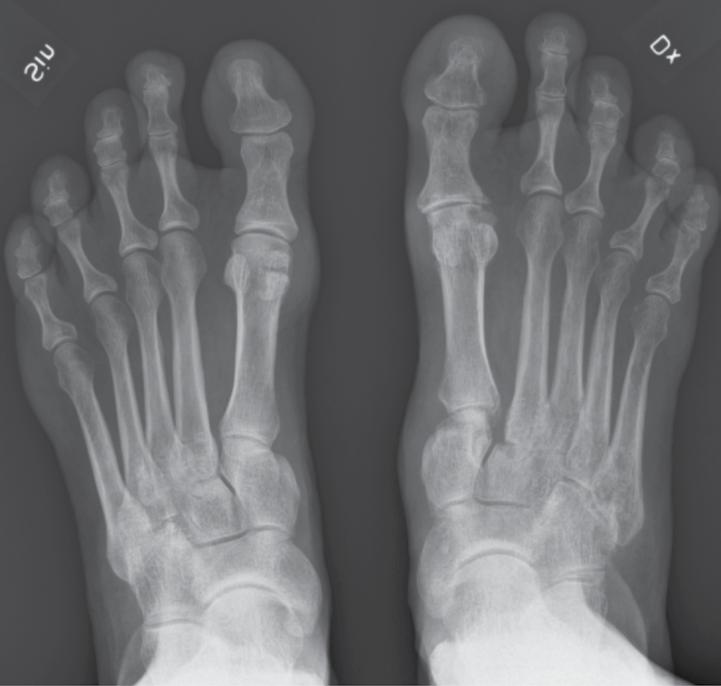

35 årig man som ådragit sig en skada av höger fot vid MC-olycka. Vid undersökning finner du att foten är svullen samt att det finns ett plantarhematom. Diffus ömhet över fot + fotled. Röntgen fotled ua. Röntgen fot: se bifogade bilder.

a. Vilken skada har inträffat? (1p)

b. Kompletterande utredning? (1p)

c. Behandling? (1p)

a. Hematomet i fotsulan och röntgenbilden talar för en allvarlig skada och att man bör misstänka en skada av Lisfrancs led. Denna

skada missas eller misstolkas ofta och ger obehandlad lätt upphov till bestående besvär.

b. Undersökningen bör kompletteras med CT.

c. Reposition och operativ fixation alternativt artrodes av skadade leder.